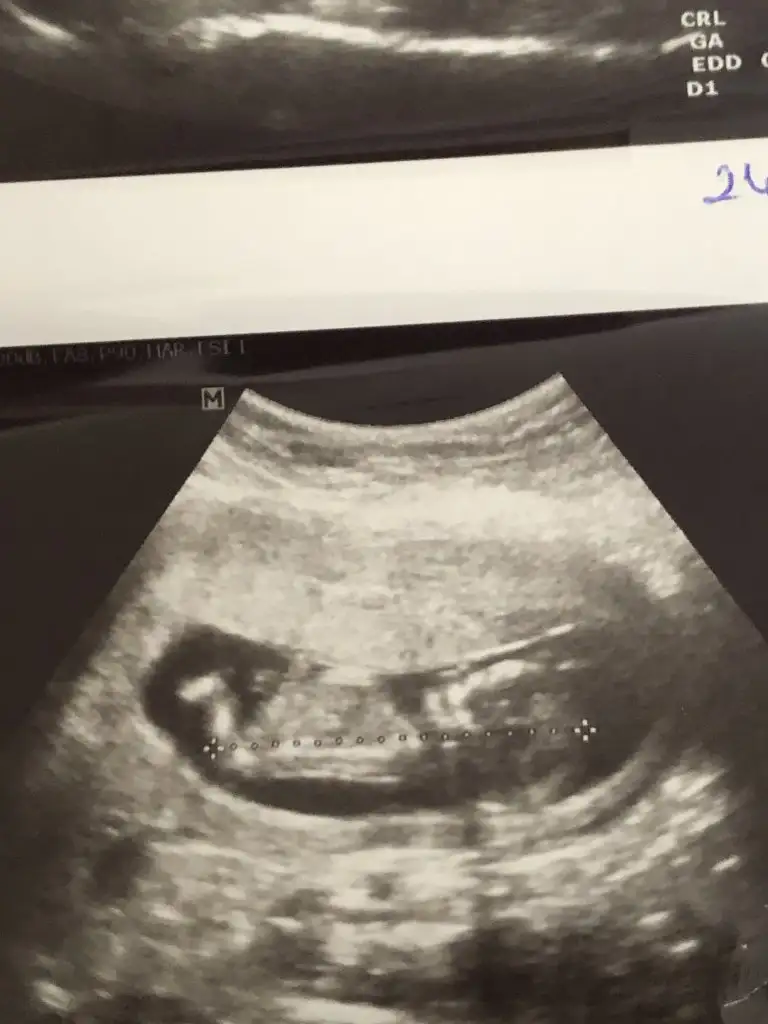

S.a Ikra meyra Ikra meyra cnm ultrason resmini alınca sana aticaktm bugüne kısmetmiş ben biseyy anlamadm ya görüntü net değil ya da ben tecrubesizim sana zahmet bakar msn sence cinsiyet ne bugün sırf cinsiyet için farkli doktora gittim 🤭☺️🤔

• IMG20200225151028.webp

IMG20200225151028.webp

35,8 KB · Görüntüleme: 53

S.a Ikra meyra Ikra meyra cnm ultrason resmini alınca sana aticaktm bugüne kısmetmiş ben biseyy anlamadm ya görüntü net değil ya da ben tecrubesizim sana zahmet bakar msn sence cinsiyet ne bugün sırf cinsiyet için farkli doktora gittim 🤭🤔